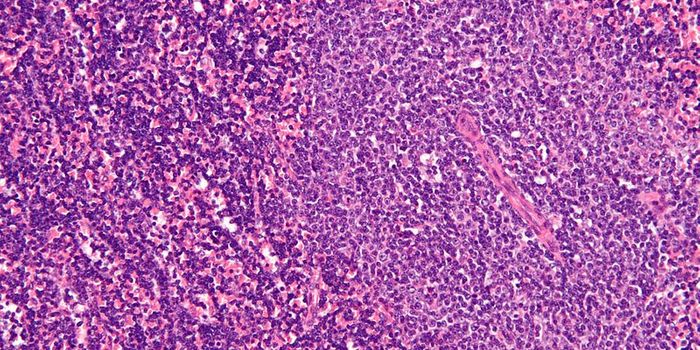

FEB 12, 2016ImmunologyAcute lymphoblastic leukemia (ALL) and non-Hodgkin’s Lymphoma (NHL) affect 75,000 and 72,000 people each year in t ...

MAR 18, 2015Immunology

After a chance observation in the lab, researchers found a method that can force dangerous leukemia cells in the l ... -

MAR 19, 2015CancerResearchers at the Stanford University School of Medicine have discovered that when a certain aggressive leukemia is cau ...

-